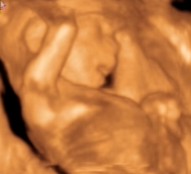

Csipet! Naaaaagy gratul a kis kukacoshoz

Maki nektek meg a tuti kiscsajhoz

De jók a képek!!